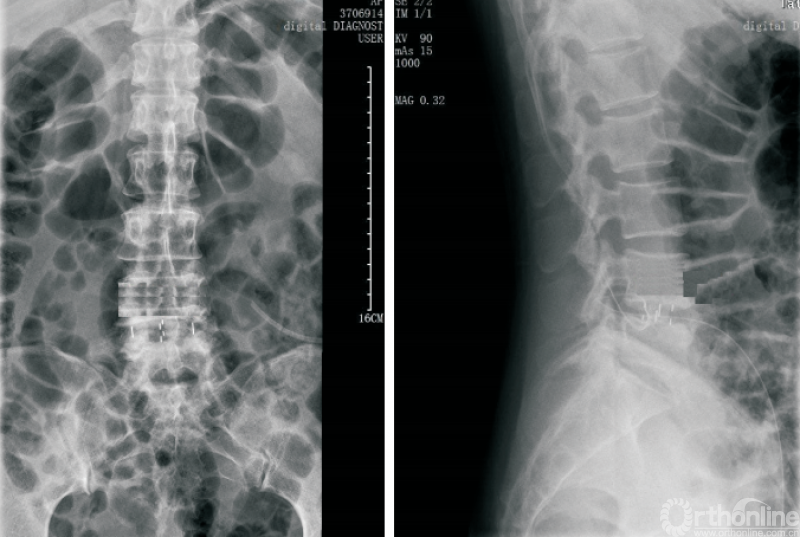

1.2 OLIF技术用于治疗退行性脊柱侧弯

相较于TLIF、PLIF等经典的手术方式,OLIF的主要优势是在更小损伤的前提下,更加有效地恢复椎间隙高度、椎间孔高度、腰椎前凸、融合节段前凸等。因此,OLIF技术在治疗退行性脊柱侧弯方面具有独特的优势(图2)。

图2 OLIF技术用于退行性脊柱侧弯的治疗

传统的后路截骨矫形手术具有手术难度大、手术时间长、手术创伤大、术中出血多等劣势,对于脊柱外科医师具有较长的学习曲线。而OLIF技术联合后路钉棒系统固定则完美避开了这些问题。

研究证实,OLIF技术联合后路钉棒系统固定治疗退行性腰椎侧凸[17-20],可以有效地纠正及缓解术后冠状位Cobb角、C7垂线与骶椎中央线的距离、腰椎前凸、骨盆倾斜、腰背部疼痛等。

相较于传统的后路截骨矫形手术,OLIF技术缩短了手术时间,减少了出血量,术中出血量仅为113~436mL。经过我院改良暴露方式[21],进一步降低了OLIF手术的手术风险,减少了放射线暴露,关键是将非完全直视的操作改为完全直视操作,使操作更加安全,学习曲线更平缓。